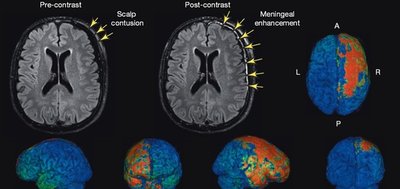

Article | What a concussion looks like inside your brain